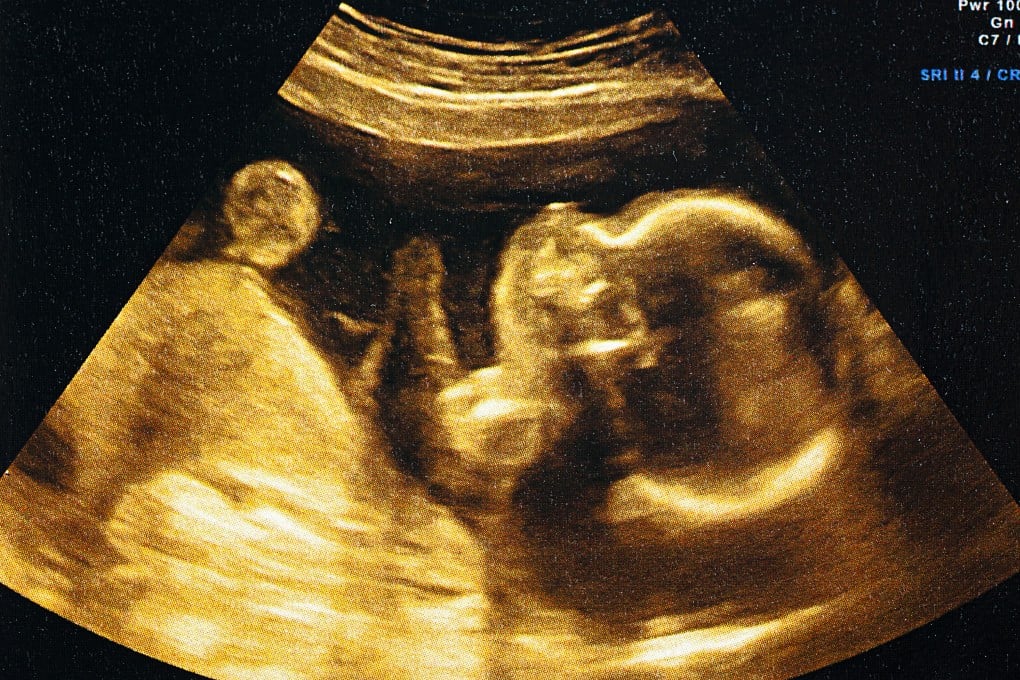

China-led team replicates human embryo ‘invasion’ of the womb for the first time

A China-led team has built the world’s first mini-womb on a chip that can fully replicate the “invasion” of human embryos in the uterus during early pregnancy.

Blastocysts are five to six-day-old embryos that consist of 100 to 200 rapidly dividing cells, including an outer cell mass that will implant into the uterus to develop into the placenta and an inner cell mass that will eventually form the baby.